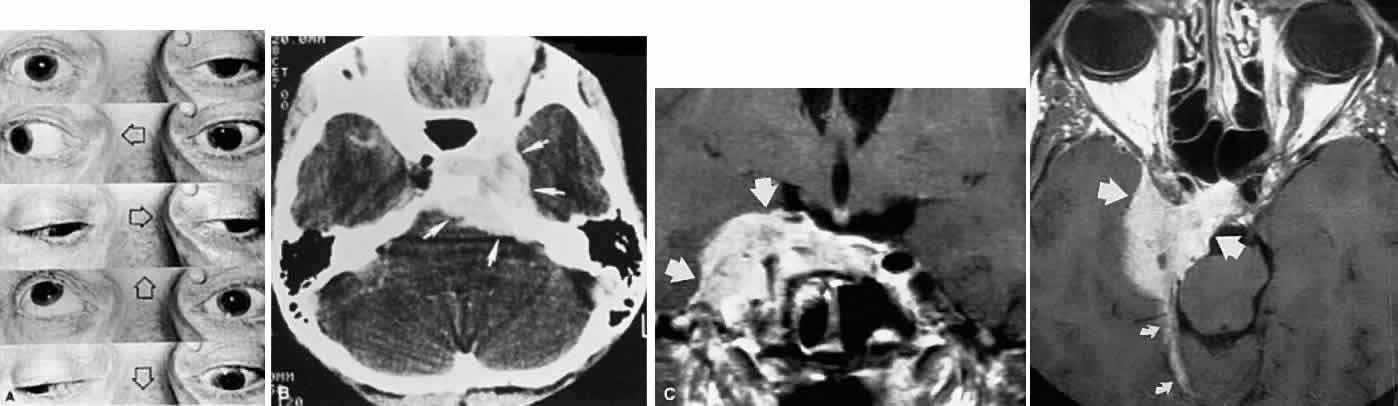

Acquired bi-nuclear total ophthalmoplegia is occasionally seen (Fig. 11), as reported by Masucci.82 These findings are the result of thrombotic or embolic processes at the level of the basilar bifurcation, with occlusion of the median mesencephalic perforating arteries. Congenital bilateral total ophthalmoplegia with or without levator and pupil sparing has been reported and may be associated with dysplasia of the corpus callosum.83

Fig. 11. Bilateral oculomotor palsies (nuclear?) associated with abrupt onset of vertigo and mild left hemiparesis.

ACUTE INFECTIOUS POLYNEUROPATHY

The bulbar variant of the Guillain-Barré syndrome (Landry ascending paralysis) often presents as a painless, rapidly progressive bilateral ophthalmoplegia. As it evolves, this cranial polyneuropathy may mimic unilateral or bilateral oculomotor palsies, but it usually progresses to a more or less total symmetric ophthalmoplegia that may include the pupils and accommodation. Lid elevators can be normal or minimally involved. The presence of acute or subacute facial diplegia confirms the diagnosis and practically excludes other considerations (Fig. 17).